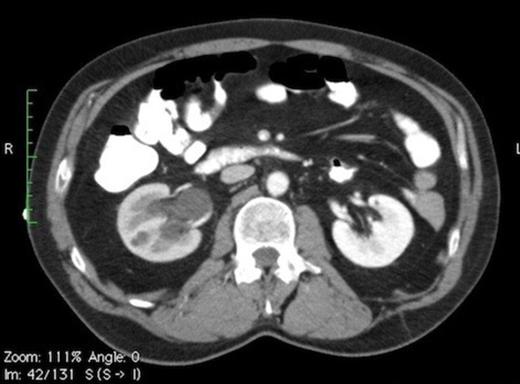

Contrast CT (Fig. 1A) depicts a thickened appendix measuring >12mm with periappendiceal fluid suggestive of acute appendicitis. Moderate hydronephrosis (Fig. 1C) of right kidney was noted with a 6mm calculus (Fig. 1B) in the right mid ureter.